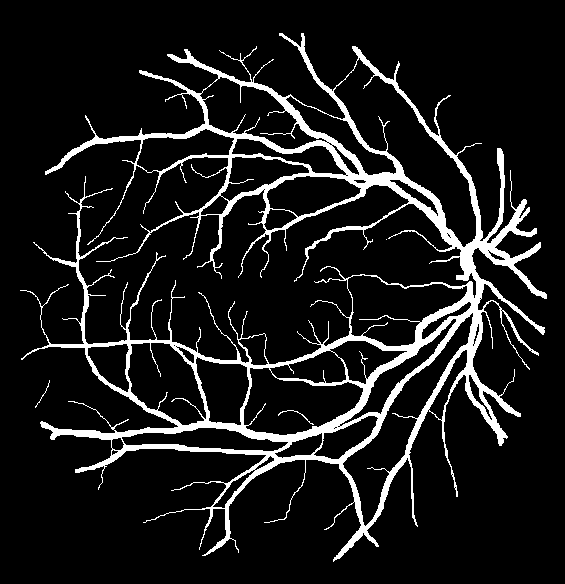

VI-A Retinal Artery and Vein Segmentation

As reported in Table IV, we compared the SegRAVIR model against competing deep learning-based segmentation approaches on the RAVIR dataset. Evidently, SegRAVIR outperforms these methods as judged by all metrics for artery and vein classes with a healthy margin. In terms of Dice score, SegRAVIR outperforms CE-NET, IterNet and AG-Net by , and for artery segmentation and by , and for vein segmentation, respectively. Fig. 4 presents a qualitative comparison of the semantic segmentation outputs of SegRAVIR, CE-Net, and U-Net. Specifically, SegRAVIR yields more accurate vessel topology (i.e., thickness and orientation) segmentation with higher pixel-wise classification accuracy.

Table V presents quantitative performance benchmarks of SegRAVIR and other competing approaches for retinal artery and vein classification on the RITE dataset [11]. SegRAVIR outperforms previous state-of-the-art approaches in terms of accuracy, sensitivity, and specificity. Fig. 5 provides a qualitative comparison between segmentation outputs of SegRAVIR and the method of Hemelings et al. [40] on the RITE test set.